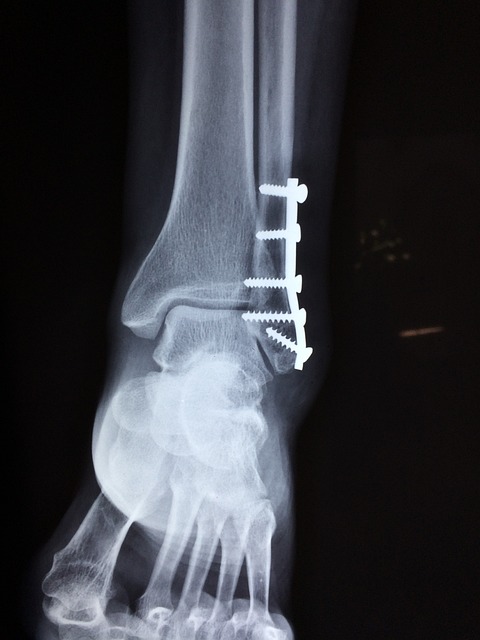

소아 골절은 부위와 형태에 따라 여러 가지로 나뉘는데, 대표적으로 다음과 같은 유형이 있습니다.

- 단순 골절: 뼈가 깨끗하게 부러지는 경우입니다.

- 그린스틱 골절: 뼈의 한쪽만 부러지고 반대쪽은 휘어진 상태입니다.

- 성장판 골절: 뼈의 성장판이 손상된 경우입니다.